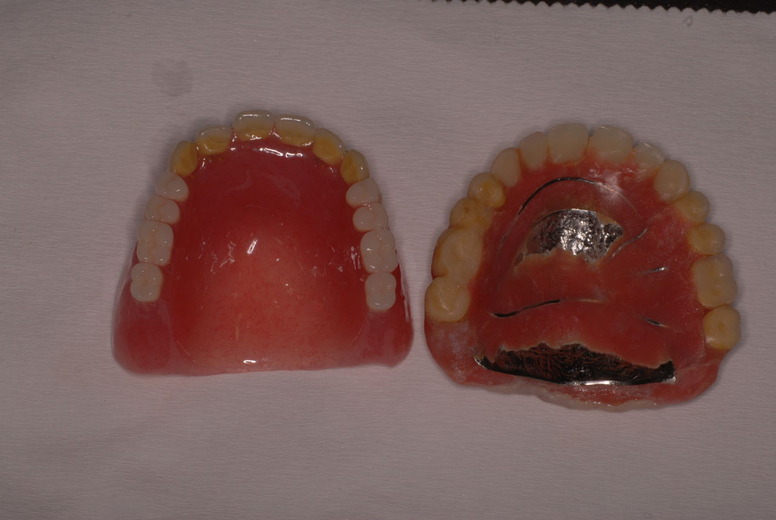

金属にもかかわらず適合が悪い為にプラスチックを重ね着した為に厚くなりしゃべりにくくなっていました。

かなり分厚い入れ歯です。

外注で完成させた入れ歯です。